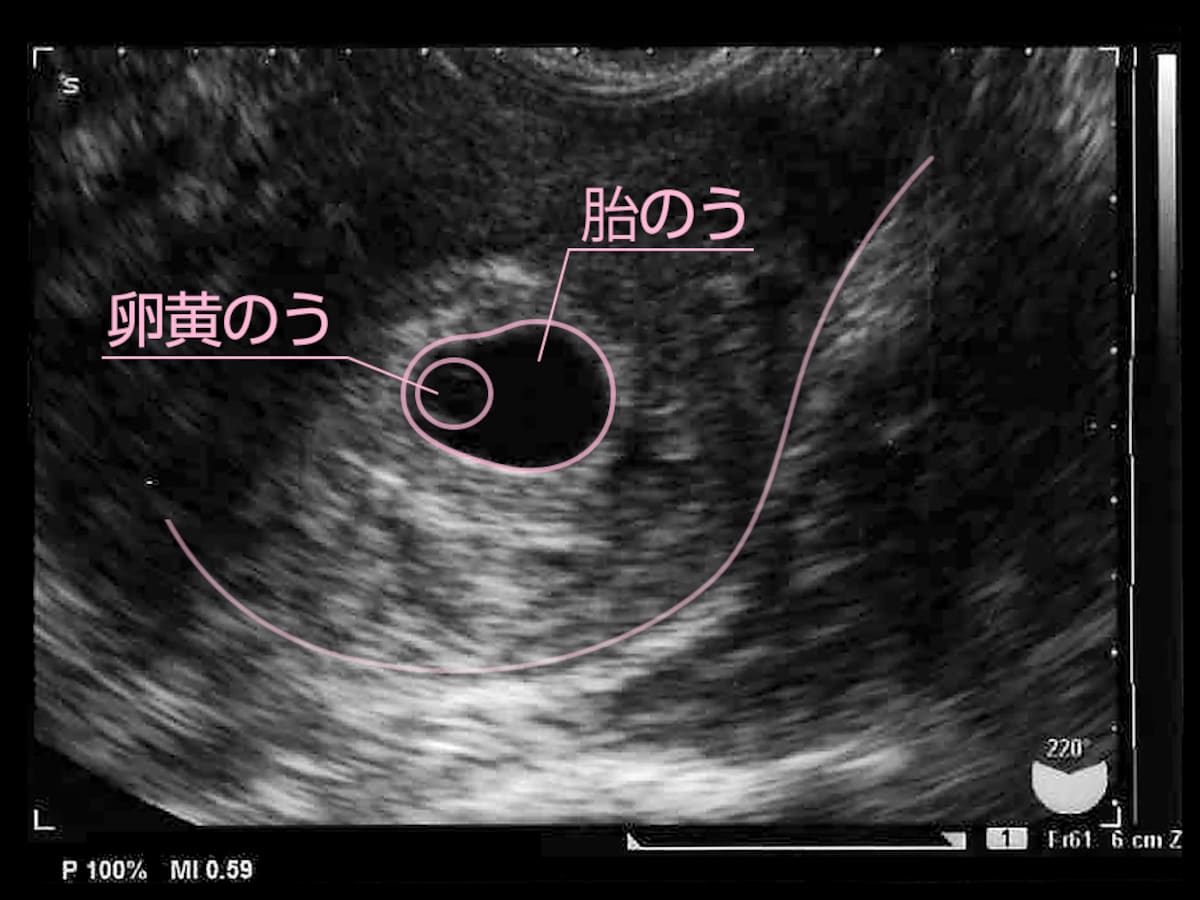

5周4日 胎嚢

妊娠5週4日 5w4d の超音波 エコー 写真

妊娠5週4日 5w4d の超音波 エコー 写真

第3話 5週4日 卵黄嚢が確認できました 胎嚢の大きくなり方物語 妊娠ぱっぴー

胎嚢見えました 妊娠2ヶ月 5週4日 の写真 ベビカム成長記録 妊娠 出産 育児に関する総合情報サイト ベビカム